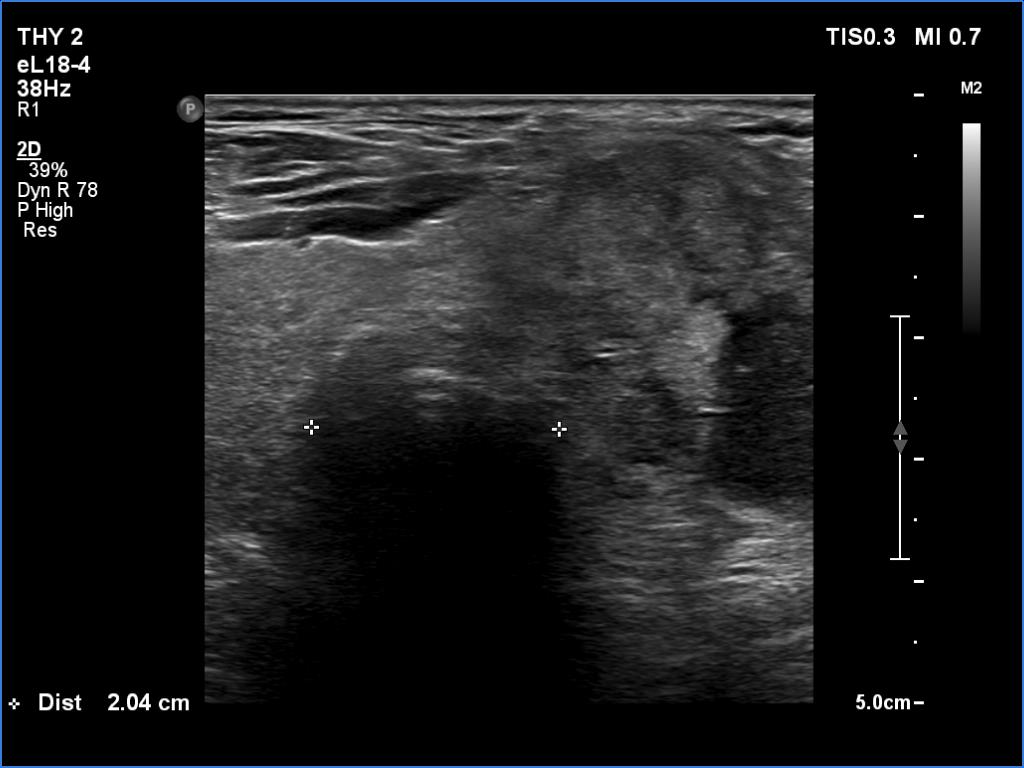

Elastography - case 1260 (ultrasonographic picture 16)

Middle portion of the neck, at the level of the upper pole of the left thyroid lobe. It is worth comparing the diameter of the trachea at this level with the lower one - see next image.